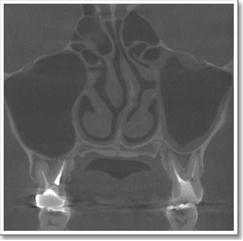

1)上顎洞炎(蓄膿症)が見つかった患者さん

上の奥歯が咬むと痛く、頭痛もありました。歯医者で何回治療をしても症状が改善せず、当院の総合健診を受診された結果、上顎洞炎(蓄膿症)が見つかった患者さんです。

1本ずつの歯に対して、精密な検査を実施することで病気の原因と進行状態が診断できます。

早く診断し、適切な治療を行った結果、患者さんは症状も消失し、歯も抜かずにすみました。

(30歳女性:以下の資料は患者さんの了解を得て載せています)

根の治療が不完全で歯根の先が化膿しています。

CT検査で上顎洞内の粘膜が肥厚(矢印)しているのがわかります。 歯根の病気で上顎洞炎(蓄膿症)になっていました。頭痛の原因は蓄膿症でした。

膿んでいた歯の治療によって腫れていた上顎洞内の粘膜も元に戻りました。 上顎洞炎(蓄膿症)も治り、症状も消失しました。